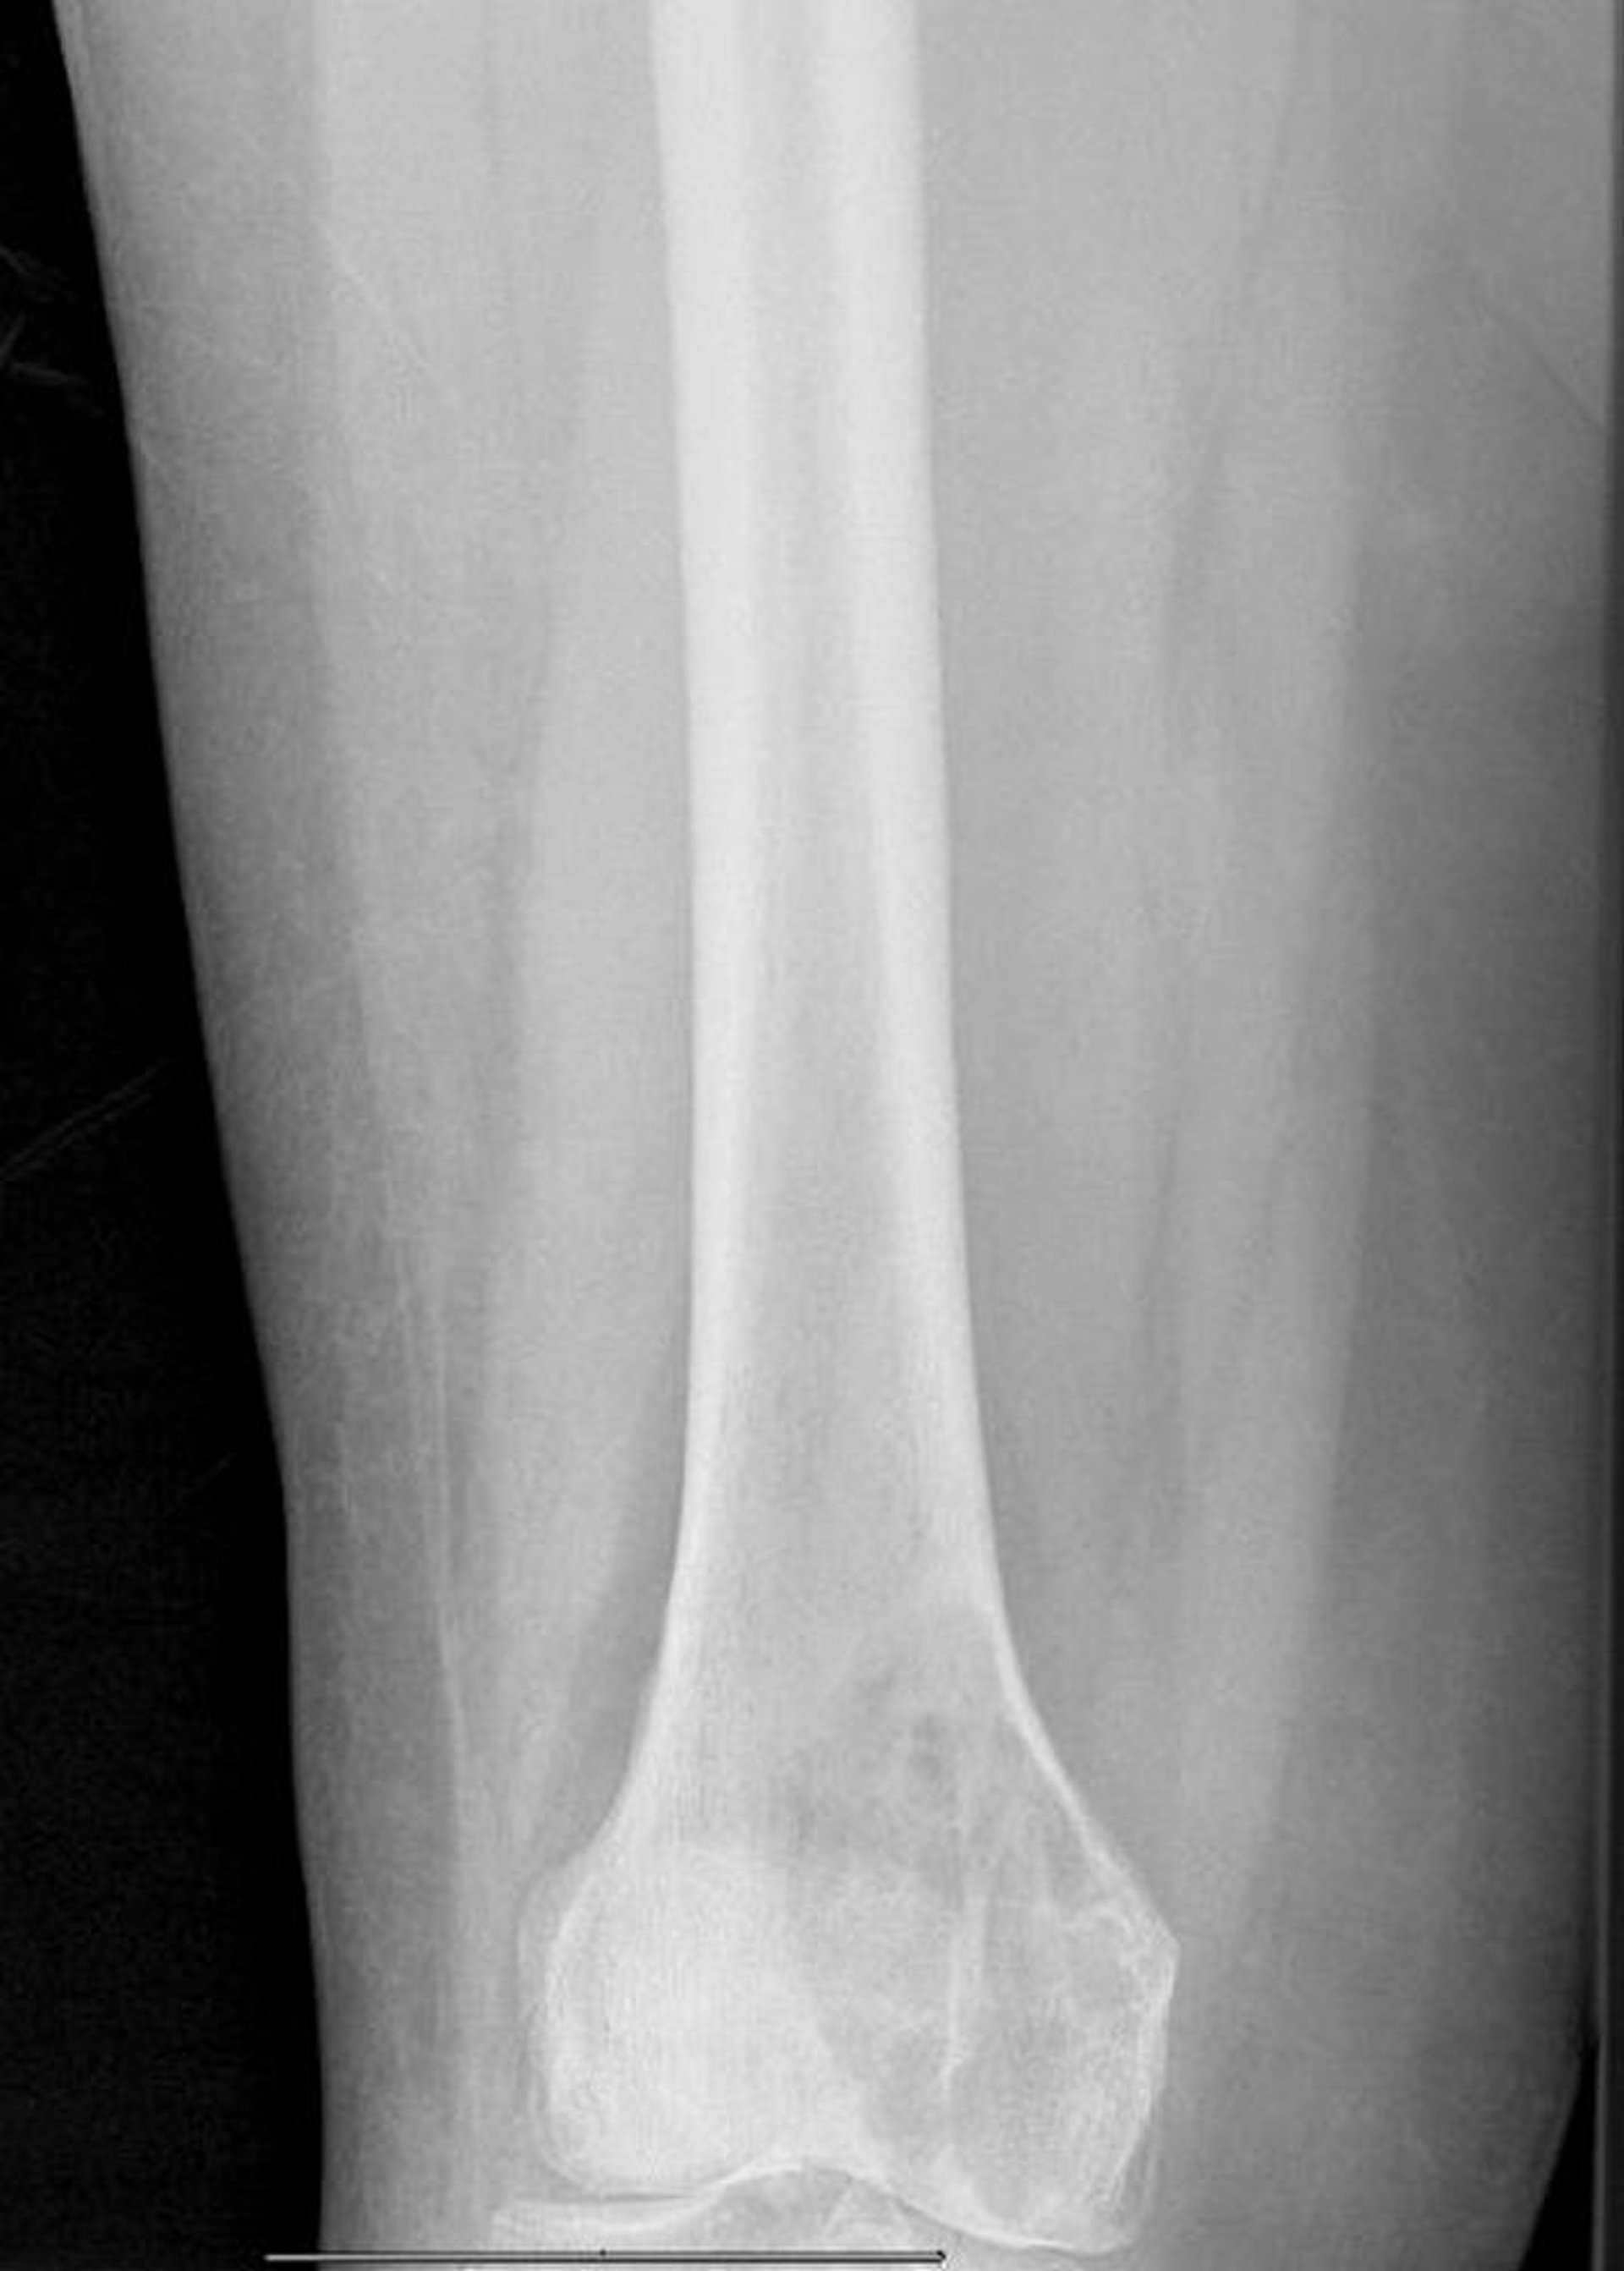

Литические метастазы в дистальной части бедренной кости

На этой рентгенограмме видно большое метастатическое литическое поражение медиального мыщелка бедренной кости с угрозой патологического перелома.

Image courtesy of Michael J. Joyce, MD, and David M. Joyce, MD.